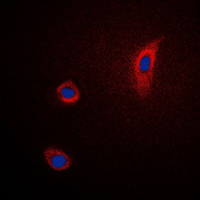

Immunofluorescent analysis of PGHS-2 staining in Jurkat cells. Formalin-fixed cells were permeabilized with 0.1% Triton X-100 in TBS for 5-10 minutes and blocked with 3% BSA-PBS for 30 minutes at room temperature. Cells were probed with the primary antibody in 3% BSA-PBS and incubated overnight at 4 °C in a humidified chamber. Cells were washed with PBST and incubated with a DyLight 594-conjugated secondary antibody (red) in PBS at room temperature in the dark. DAPI was used to stain the cell nuclei (blue).